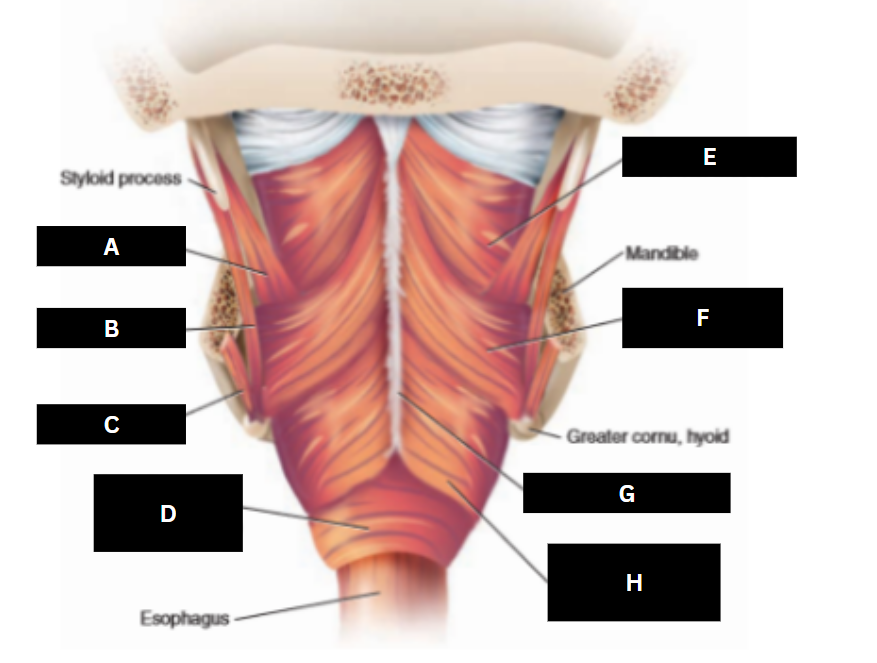

Stylopharyngeus

A

Styloglossus

B

Stylohyoid

C

Cricopharyngeus

D

Superior pharyngeal constrictor

E

Middle pharyngeal constrictor

F

Pharyngeal raphe

G

Inferior pharyngeal constrictor

H